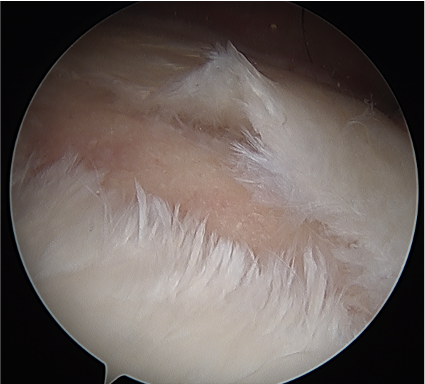

Arthroscopic posterior labral repair / capsular plication

Technique

- posterior labral repair

Posterior labral repair

Posterior capsular plication